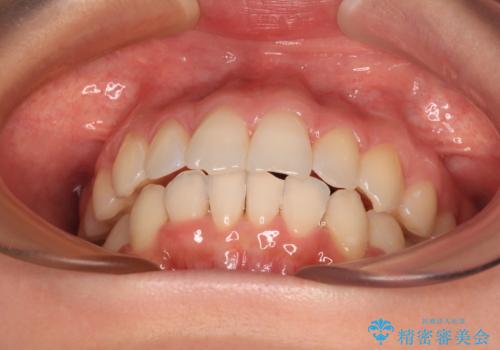

- 前歯のデコボコで前方に出ていることを気にして来院された患者様です。

上顎前歯が捻れて前方に飛び出しており、下顎前歯もそれに沿うようにデコボコとなっていました。

IPR(歯と歯の間を削る処置)によりスペースを獲得して上下顎前歯のデコボコを改善し、飛び出している前歯が引っ込むように設定し、インビザラインにて矯正治療を行うこととしました。